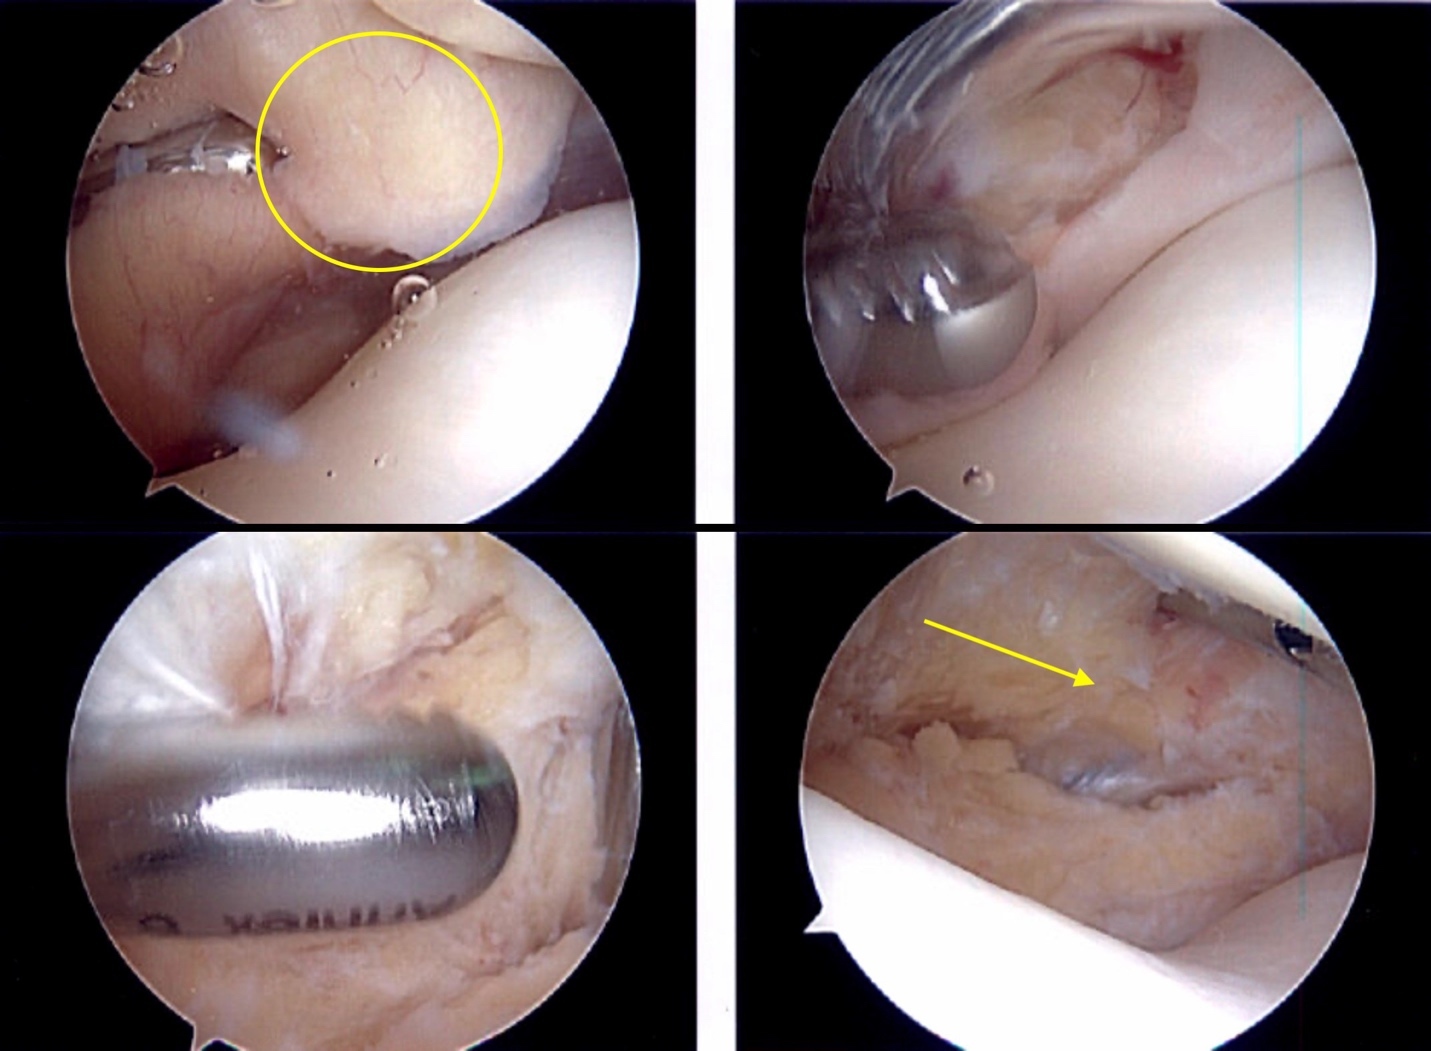

Using the same technique described in Case 1,16 thick bands of fibrotic scar tissue were identified on the posterior surface of the markedly enlarged infrapatellar fat pad (Figure 4). Following resection of three-quarters of the fat pad, the arthroscope was then placed in the standard anterolateral portal to carry out further diagnostic exam.

In the first month post op, he noted resolution of his anterior knee pain and sought out a second arthroscopic fat pad resection on his contralateral knee. Eight weeks after his initial surgery, the left sided arthroscopic fat pad resection was performed, using the same technique. Again, he was found to have a markedly enlarged thickened and fibrotic fat pad. This was carefully resected, with the patellar tendon protected.

In both of the presented cases, a superolateral viewing portal was utilized which the authors feel is absolutely crucial in adequately observing the infrapatellar fibrosis that would otherwise be missed with a 30-degree scope through standard inferior viewing portals. The complete description of this technique has been previously reported.16 In short, this technique protects the patellar tendon by creating an interval between the tendon and fat pad bluntly with the use of Metzenbaum scissors through the standard anterolateral and anteromedial arthroscopic portals. Additionally, it is important to adequately visualize the anterior horn of the medial and lateral menisci, as they could be at risk in this technique particularly with overzealous use of the arthroscopic shaver in the anterior interval. In the case of any subacute or chronic limitations in range of motion, additional post operative implementation of arthrofibrosis protocol is encouraged with particular focus on a gentle overpressure program.17